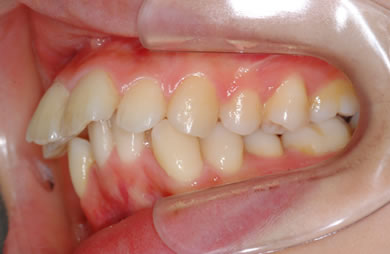

| 性別/年齢 | 女性 / 26歳 | ||||||||||||||||||||||||||||||||

| 主訴 | 上下乱ぐい歯と出っ歯を治したい。 | ||||||||||||||||||||||||||||||||

| 治療方針 | 口元が出ていていること、がたつきが大きいことより、上下左右の第一小臼歯および親知らずを抜歯し、マルチブラケット治療を行う。抜歯した隙間を活用できるよう上顎にはインプラントアンカー(釘)を使用し、その釘より歯を後ろに移動する。 | ||||||||||||||||||||||||||||||||

| 治療内容 | 唇側矯正(シルバー)、矯正用スピードインプラント、ハイブリッドセラミックインレー2本 | ||||||||||||||||||||||||||||||||